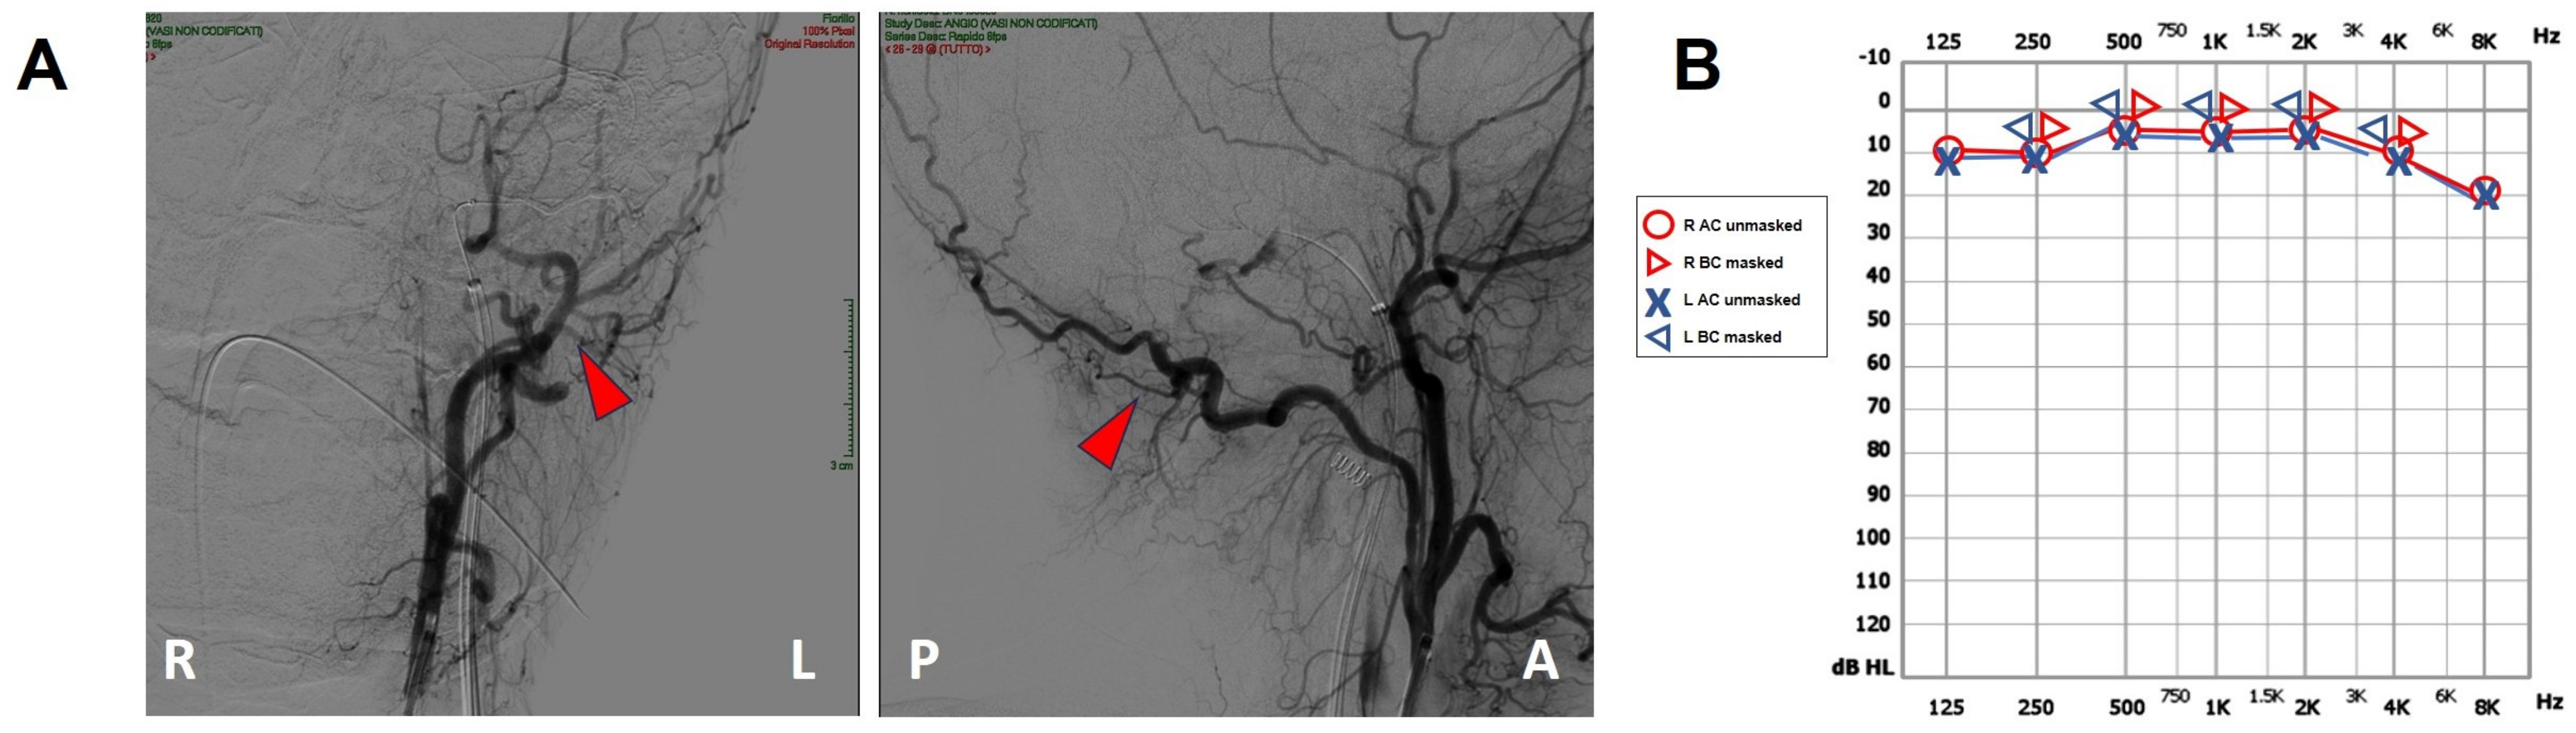

Figure 4.

Post-operative findings. (A) Coronal (right side) and sagittal (left side) projections of the intracranial DSA showing the sole left occipital artery (red arrowhead). Neither DAVF nor transverse sinus can be detected. (B) Pure tone audiometry showing normalization of the AC threshold on the left side with closure of the ABG. A: anterior, ABG: air–bone gap, AC: air-conducted, BC: bone-conducted, DSA: digital subtraction angiography, L: left, MRI: magnetic resonance imaging, P: posterior, R: right.